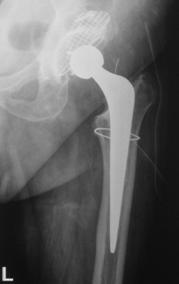

2. Clasificarea Vancouver a fracturilor periprotetice.

Acesti factori au fost adunati in clasificarea Vancouver.

In functie de localizare fracturile se impart in trei categorii:

Fracturile de tip B se localizeaza periprotetic sau se extind usor inferior de varful cozii protezei. Tratamentul acestor fracturi depinde atat de stabilitatea componentei femurale cat si de calitatea capitalului osos restant. Subtipul B1 cuprinde fracturile periprotetice care nu afecteaza stabilitatea protezei, iar in subtipul B2 sunt incluse fracturile ce afecteaza fixarea protezei. In ambele cazuri capitalul osos restant este satisfacator. Fracturile ce produc afectarea fixarii protezei, produse datorita osteopeniei sau osteolizei, si cele cominutive sunt incluse in subtipul B3. In aceste cazuri este necesara reconstructia partii proximale a femurului inainte de a putea efectua artroplastia de revizie.